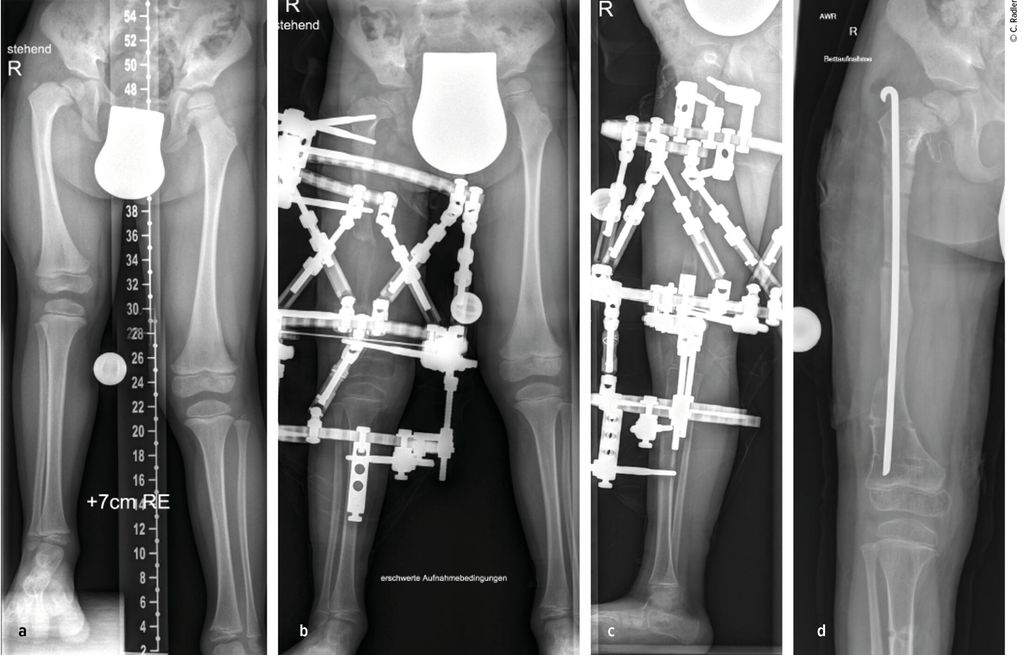

Die Valgusstellung kann sehr einfach über eine Wachstumslenkung (Hemiepiphysiodese mit 2-Loch-Platte) korrigiert werden. Um eine Subluxation am Kniegelenk zu verhindern, muss bei allen diesen Fällen bei Verlängerung mit Fixateur dieser knieüberbrückend montiert werden (Abb.4). Bei Verlängerung über einen Verlängerungsmarknagel wird in diesen Fällen eine Oberunterschenkelschiene (KAFO) verwendet und prophylaktisch, soweit noch vorhanden, die Fascia lata auf Höhe des oberen Patellapols durchtrennt. Bei deutlicher Instabilität oder auch Subluxation ist eine Stabilisierung über eine komplexe Operation, die als Super-Knee-Operation subsumiert wird, erforderlich.2 Diese Operation kann auch an die Hüftrekonstruktion/Super-Hip-Operation angeschlossen werden, da hier die Faszie ohnehin präpariert wird. Je nach Alter des Patienten und dem Ausmaß der Instabilität wird hierbei die Fascia lata nach Präparation bis an das Tuberculum Gerdyi und Halbieren der Länge nach entweder extraartikulär oder intraartikulär geführt. Auch die Fixation wird abhängig vom Alter mit Biotenodeseschrauben oder Weichteilzügelung durchgeführt.

Abb. 4: Platzierung (a–d) eines Fixateur externe mit Knie-Überbau (e–g) zum Schutz vor (Sub-)Luxation